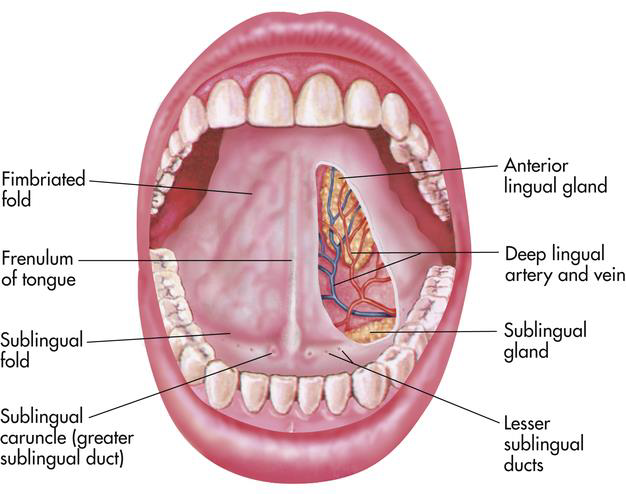

Floor

- Sublingual papilla (caruncle)

- Submandibular g. 開口

Sublingual space

- Lingual n./a.

- Hypoglossal n.

- Sublingual a.